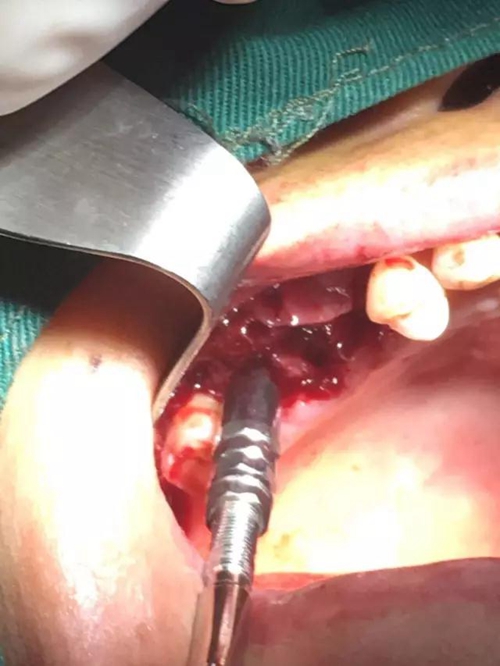

【病例分享】?jī)?nèi)提,用自體骨柱,不用骨粉

1.jpg